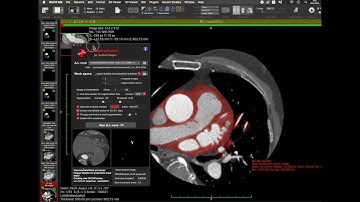

Semi-Automatic Segmentation in Osirix